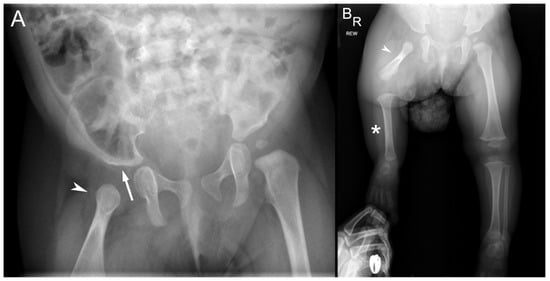

2.2. Case 2

2.3. Case 3